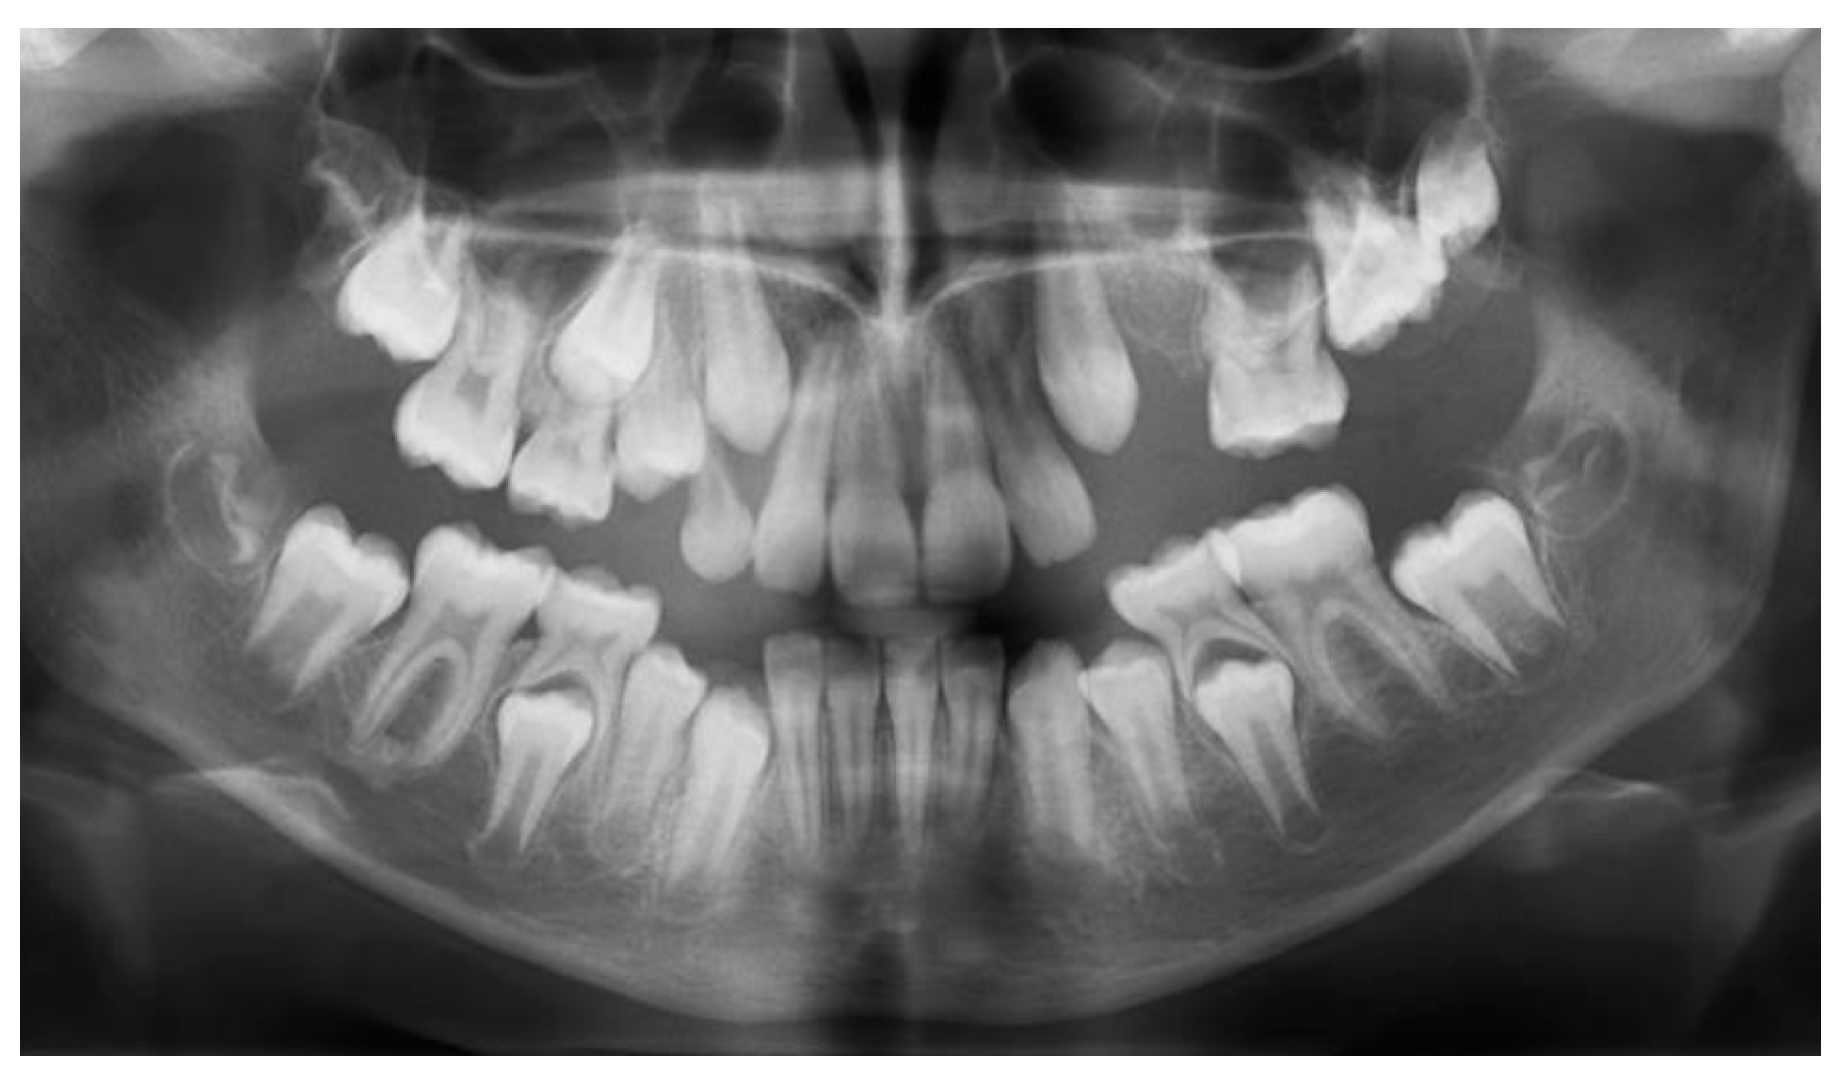

At the age of 9 y and 7 m, 26 was still not on the arch (Figure 4a). A cone beam computed tomography (CBCT) examination was performed. Agenesis of 24 and 25 became certain (Figure 4b), and no areas of ankylose in teeth with eruption failure were found. A decision was taken to remove 63 in order to favor the eruption of mechanically impacted 64, but extraction was postponed at the family’s request.

Figure 4.

Age of 9 y and 7 m. (a) Occlusal view of the upper arch; (b) CBCT confirmed agenesis of 24, 25, and impaction of 64.